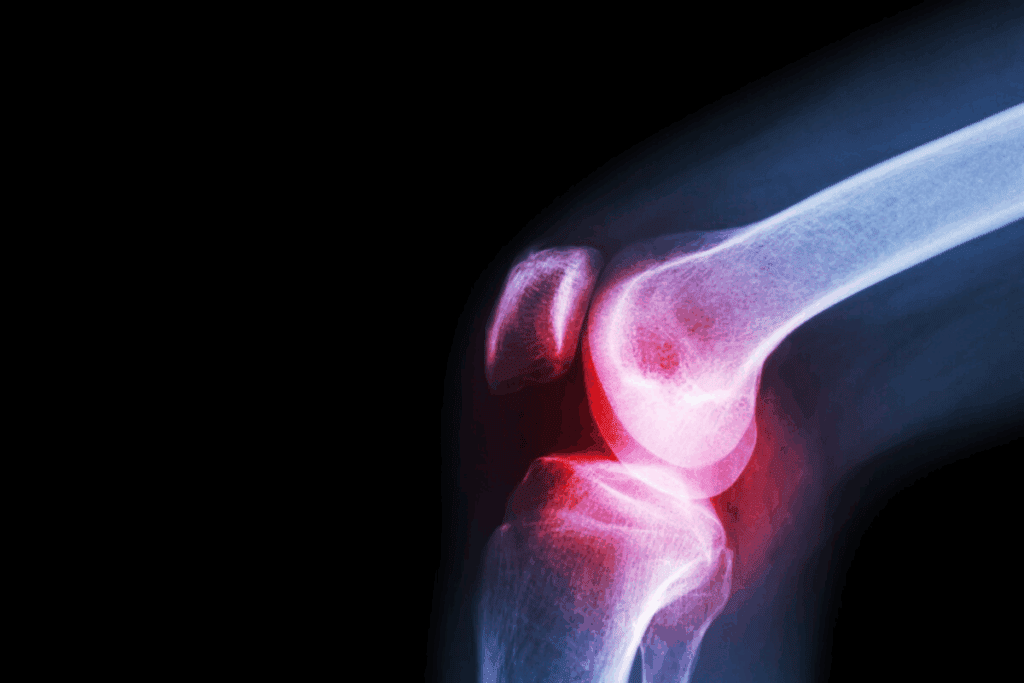

Bone Pain and Skeletal Complications

Bone pain is a key symptom of bone marrow cancer. It happens when cancer cells grow in the bone marrow. This can weaken bones and cause fractures.

People with bone marrow cancer often feel pain in their back, ribs, or hips. This pain can be constant and uncomfortable.